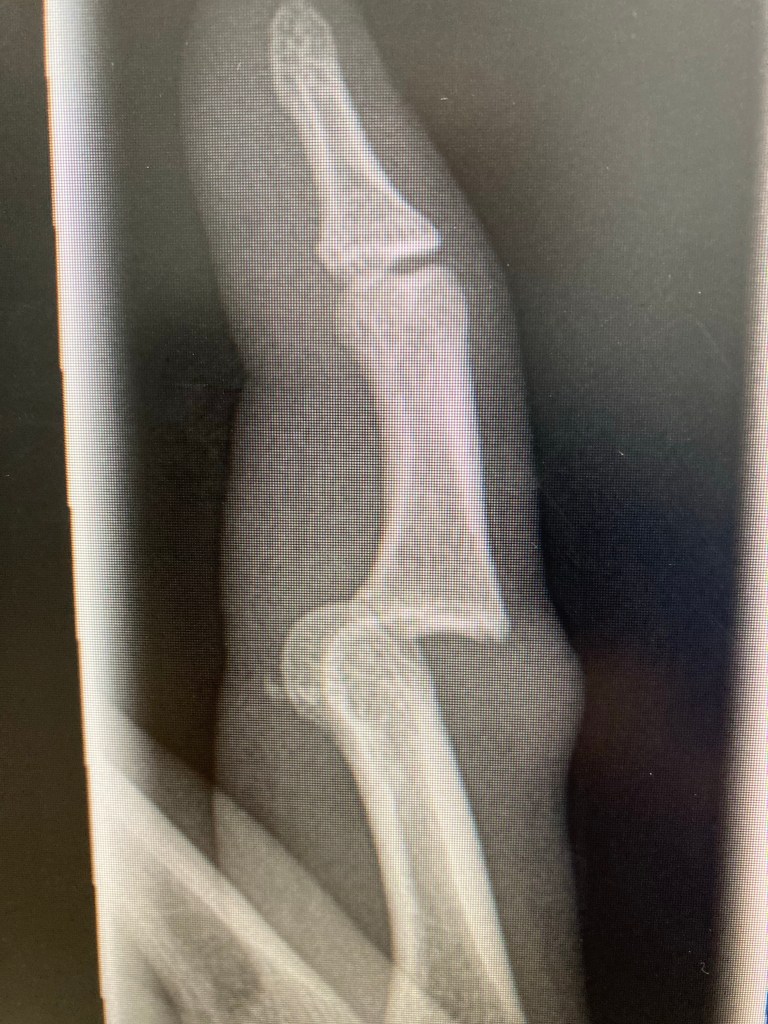

Pat came straight over to me, a bit anxious. “I think I’ve broke my finger.”

I didn’t think he would have, as he’d not had much to do since the third goal. He said he couldn’t bend it as he took his glove off. He’d definitely done something.

So that was that. He took his other glove off and his shirt and passed them to Jack, the midfielder and stand in keeper and I took Pat to hospital. On the way there I asked him how he’d done it. It was definitely on the third goal but he wasn’t sure if it was when he got a hand to the ball, or if he’d landed on it. Either way, he’d carried on until half time. At the hospital, we were waiting a few hours to be seen by the triage but once we’d got in and he’d had an x-ray, it only took about half an hour and we were on our way back to the car.

The nurse that looked after Pat was a football fan and his daughter a keeper, so I think we might have had a bit of preferential treatment from an unexpected part of the goalkeeper’s union. Pat’s finger was dislocated and while he was on the gas and air with the nurse manipulating it back into position, he was definitely under the influence, laid back giggling.

Pat had to go back to hospital to the Hand Clinic the following day where they gave him a compression dressing, some exercises to do to help it heal and also said that as well as dislocating his finger, he’d fractured it as well. Estimated recovery time was anything up to 6 weeks depending on how well the swelling went down.

The bruising came out straight away and Pat did his best to keep moving it and do the exercises from the hospital. He was back in action after 3 weeks out.